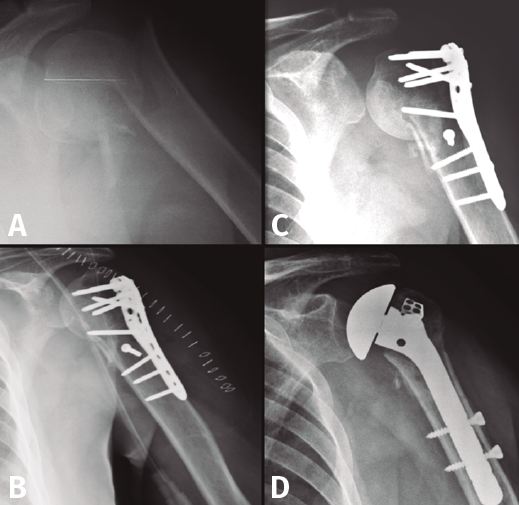

La HA en pacientes en edad laboral es también una opción de rescate ante un fracaso de osteosíntesis o tras una osteonecrosis (Figura 4). Hoy en día podemos encontrar artroplastias modulares que son reconvertibles si fuera necesario a una prótesis invertida sin tener que retirar el vástago. - Prótesis invertidas (RSA). Vistos los resultados no del todo satisfactorios de las HA por la no consolidación de las tuberosidades, se empezaron a colocar RSA en pacientes mayores con fracturas desplazadas, sobre todo en el contexto de roturas del manguito. Con estas prótesis se consigue buenos resultados en cuanto a dolor y una movilidad satisfactoria en pacientes con pocas demandas funcionales. La RSA es una intervención agresiva que deja menos stock óseo en caso de necesitar una revisión. En nuestro grupo de pacientes en edad laboral es muy infrecuente necesitar de entrada resolver una fractura de húmero proximal con una RSA, pero es una opción que tenemos que tener en cuenta. Se han desarrollado también implantes con minivástagos o de apoyo metafisario que permitirían menor pérdida de stock óseo y una revisión menos complicada si fuera necesario.

Figura 4. Evolución radiológica de una osteosíntesis de una fractura de húmero proximal izquierdo. A: radiología preoperatoria; B: osteosíntesis con placa; C: fallo en varo de la osteosíntesis; D: implantación de una hemiartroplastia.